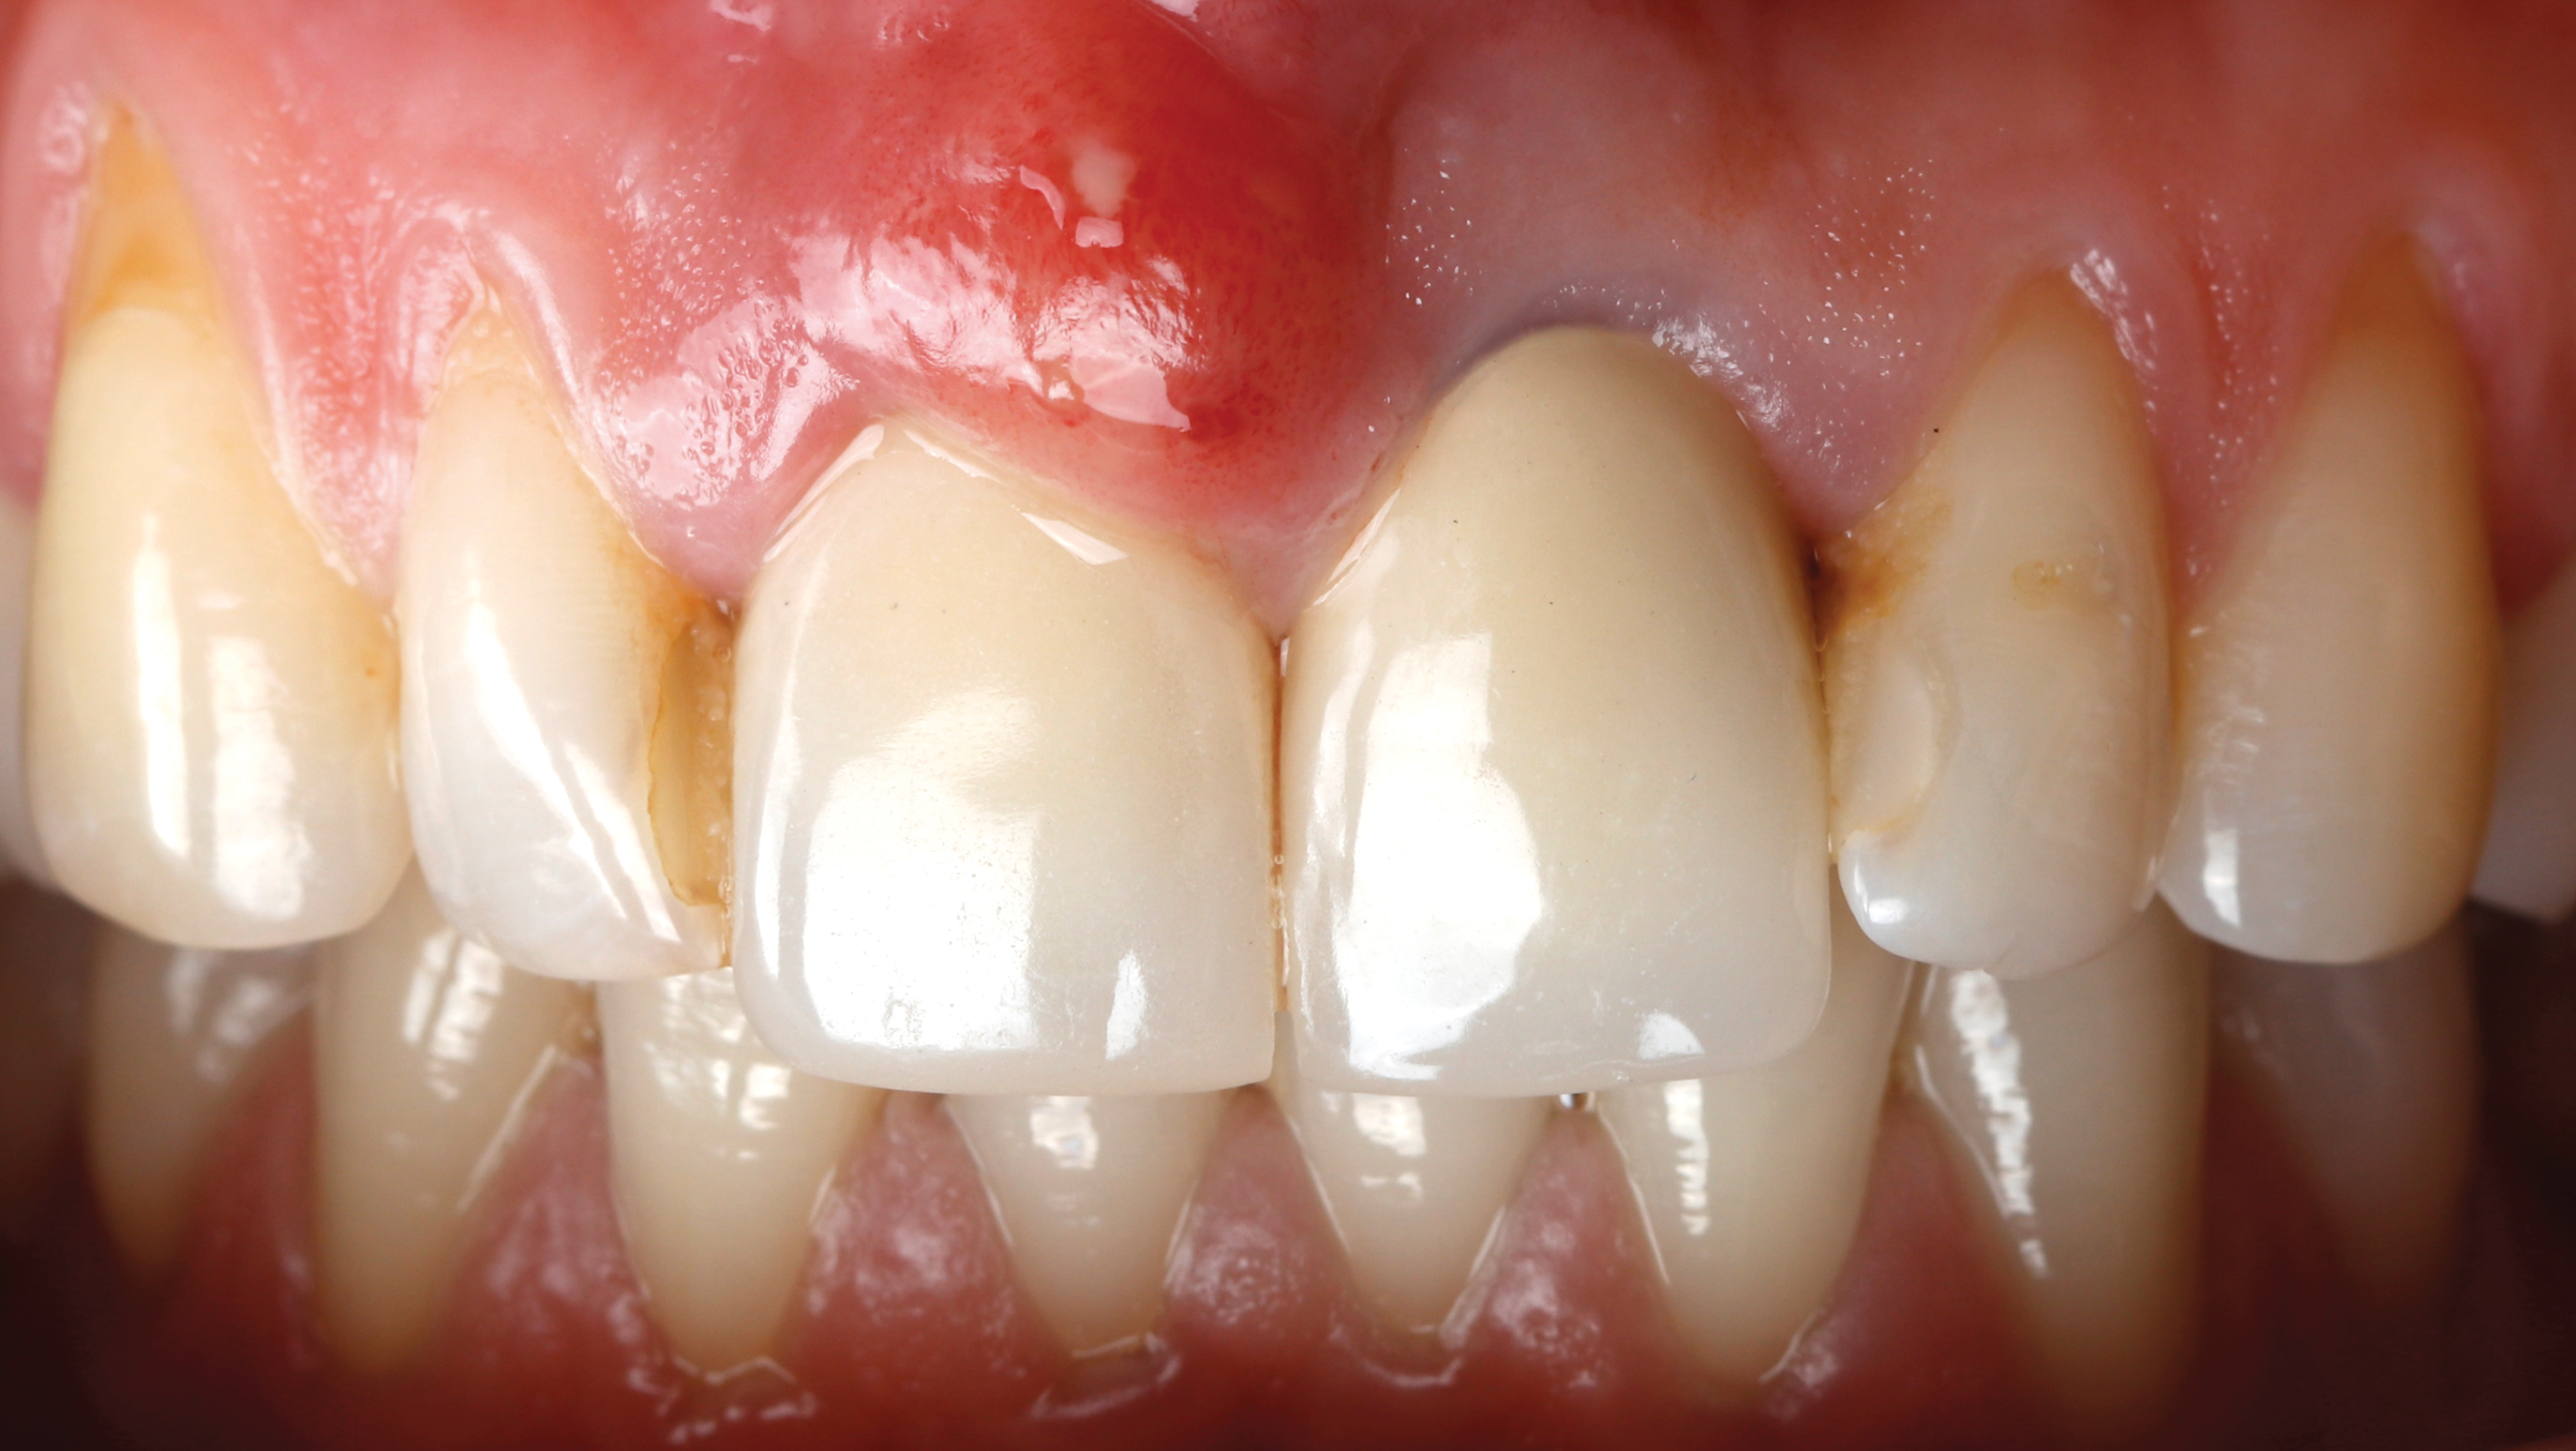

Fig 2. Case presentation of SPOT technique used on central incisor. Initial presentation, facial view, of maxillary right central incisor with hopeless prognosis due to subgingival caries and horizontal fracture.

Figure 2